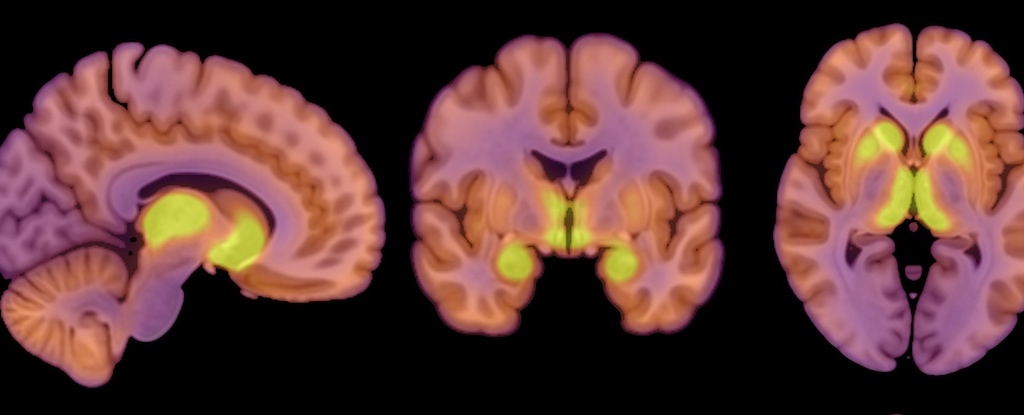

Вчені з’ясували, що у пацієнтів з анорексією спостерігається підвищена активність мю-опіоїдних рецепторів (MOR), які відіграють ключову роль у регуляції апетиту та відчуття задоволення від їжі. Аналіз мозкової активності за допомогою позитронно-емісійної томографії (ПЕТ) також показав, що мозок анорексичних пацієнтів зберігає споживання глюкози на рівні здорових людей, навіть коли організм відчуває дефіцит енергії.